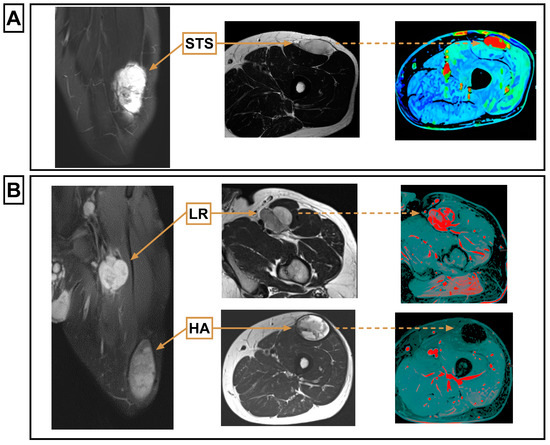

| HA | Hematoma |

| LR | Local recurrence |

| Overall MRI feature similarity | Similar to primary STS in all features (26/26) | Differed from primary STS in at least one feature (9/9) | |||